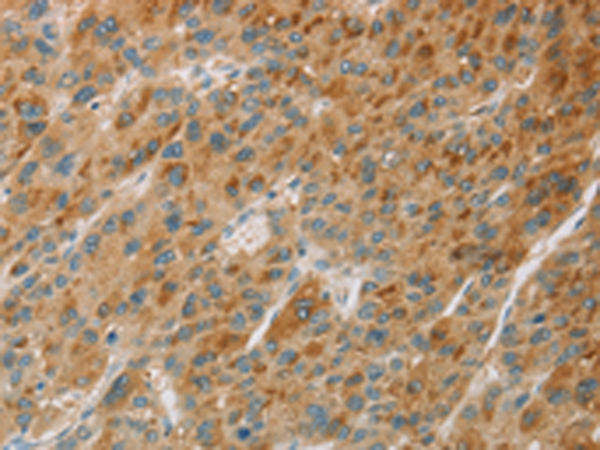

分类: 科研抗体货号: P08181别名: Aeg2; CRS3; SGP28; CRISP-3; dJ442L6.3应用: IHC反应种属: Human